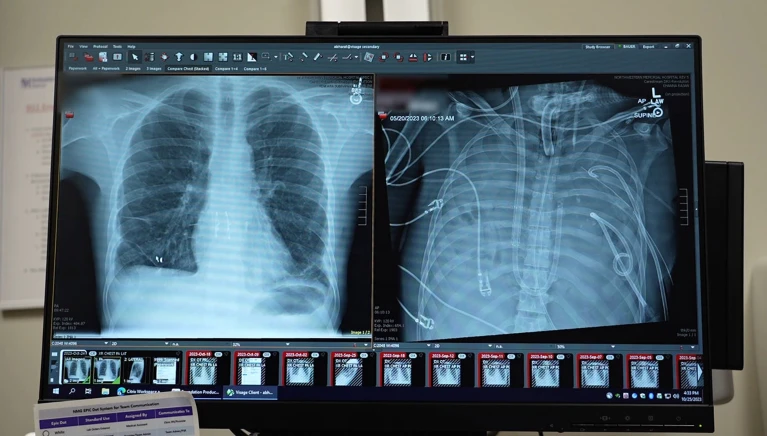

数字显示屏上的两张X光片,分别显示患者的新肺(左)与旧肺(右)。

X光片显示一名33岁患者的新肺(左)和旧肺(右)。图片来源:美国西北大学医学院